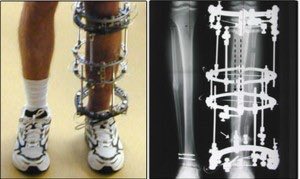

يستمع لكلام البروفيسور بإنتباه شديد لكل التفاصيل .. يقوم البروفيسور بطلب الاستشاري المختص لجهاز اليزاروف والاستشاري المختص لحالات النيورو اورثوبيدك

نقاش طويل لمدة ساعة .. انتهى بموافقة الفريق الطبي على الخطة العلاجية وتحديد مواعيد العمليات

في عام ٢٠٢٠ م تم الانتهاء من تعديل محور الطرف السفلي وبناء كتلة عضلية ممتازة والان يستطيع الطفل المشي دون اي وسيلة مساعدة

الطفل سعيد جداً ونحن اسعد بتلك النتيجة .. هنا يتدخل استشاري النيورو اورثوبيدك ويقترح تحسين وظيفة القدم !

لكن العصب ازيل ولا يمكن زراعته مرة اخرى